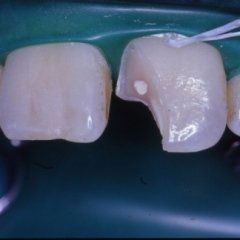

Odontoiatria e conservativa

L’enorme diffusione ancora oggi riscontrabile della carie dentaria, unita a traumi, difetti di mineralizzazione o ipoplasie dello smalto determinano la necessità di dover ricorrere ad un restauro dei tessuti dentari lesionati. Il continuo miglioramento dei materiali e di conseguenza delle tecniche hanno altresì ampliato il raggio di azione della cosiddetta conservativa che con il ricorso al trattamento endodontico in caso di lesioni particolarmente gravi, occupa circa i due terzi dell’attività del dentista. In considerazione di questo fatto quindi, oltre all’evidenza che il trattamento restaurativo diretto è in genere il primo atto odontoiatrico che si effettua su una corona dentale lesionata, emerge la necessità che questa terapia sia ben eseguita ed in armonico rapporto con le strutture parodontali ed endodontiche.